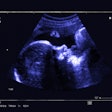

Hammou was a past president of the Mediterranean and African Society of Ultrasound. Her research interests included radiation protection and patient safety, pediatric radiology, and ultrasound.